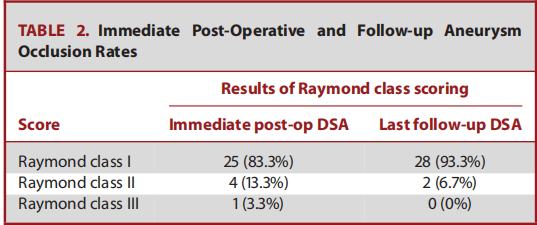

使用Neuroform Atlas支架用于Y型支架辅助栓塞技术,来治疗复杂性分叉动脉瘤。宽颈动脉瘤是指瘤体最大直径与瘤颈的比<2或颈径>4mm的动脉瘤。复杂的分叉动脉瘤定义为累及至少两个分支的宽颈分叉动脉瘤。在手术过程中,微导管超选时,首先在微导管到位困难的侧支血管内置入Excelsior SL-10(Stryker)微导管,然后另一个内径为0.0165英寸的微导管(Excelsior SL-10 or Headway 17; MicroVention/Terumo, Tustin, California)置入动脉瘤瘤体内。将第一个Neuroform Atlas支架释放到微导管到位存在困难的侧支血管内。随后以第一个Neuroform Atlas支架作为支撑,将同一Excelsior导管输送至第二分支,置入第二枚Atlas支架,与第一枚支架形成Y型支架。随后对动脉瘤进行致密栓塞。分别在术后即刻、术后3-6个月和9-15个月时进行DSA随访,采用Raymond–Roy (RR) 分级和载瘤动脉的畅通性来评估动脉瘤栓塞效果。采用改良的Rankin量表(mRS)对患者术前、术后即刻、出院、术后3-6个月和9-15个月的神经系统状况进行评估。记录患者术后出现的全部不良临床症状或体征,及围手术期和延迟并发症情况。

本研究回顾性分析了30例动脉瘤患者(20名女性)(表1)。纳入研究患者的平均年龄为52.4±8.9岁(34-66岁)。动脉瘤的瘤体最大直径为6.9±2.2 mm(4-16 mm)(图1)。分叉侧支的平均直径为2.2±0.3 mm(范围1.6-2.9 mm)。在支架展开或动脉瘤填塞的过程中,无操作相关并发症。术后即刻造影显示RR分级1级,2级,3级的患者例数分别为25例(83.3%),4例(13.3%),1例(3.3%)。无患者死亡,术后即刻神经系统检查较术前无变化。DSA造影随访平均时间为11.8±7.8月(6-36 月)。2名患者(6.7%)发生了围手术期(3.3%)或延迟并发症(3.3%)。上述延迟并发症导致患者永久性致残(3.3%)。全部患者的最终随访DSA结果显示:28例患者达到RR 1级闭塞(93.3%),2例患者实现RR 2级闭塞(6.7%)(表2)。在30例患者中,有28例患者临床随访显示mRS评分为0分。发生延迟性缺血性并发症的患者最终mRS评分为4分。一名术前mRS评分为2的患者术后随访mRS评分没有任何变化。